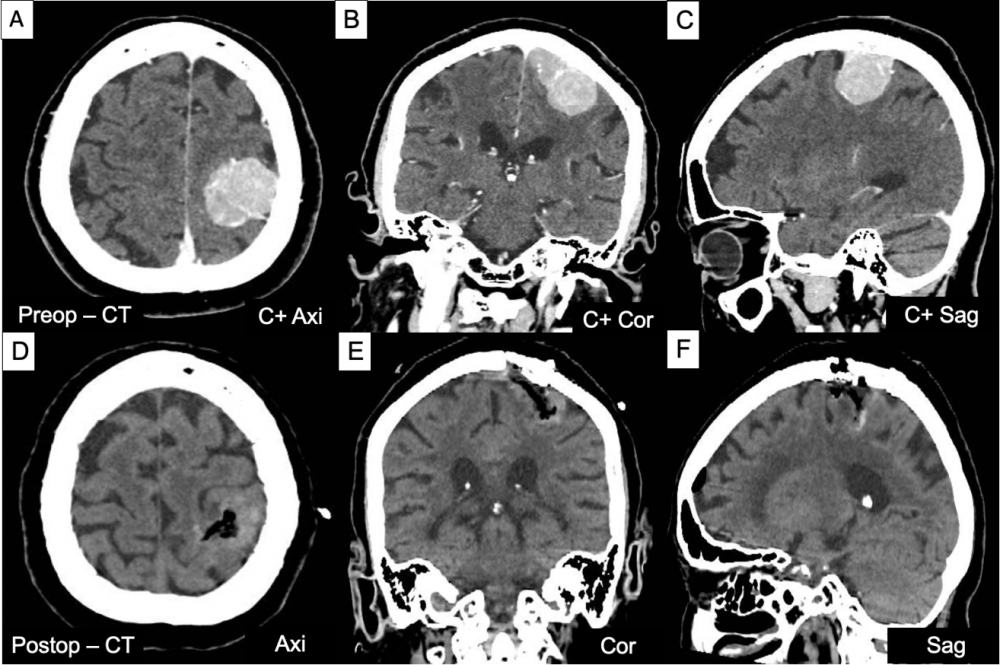

Hình 3. Hình ảnh CT scan trước mổ (A-C) với khối u vùng đỉnh trái kích thước # 4,2 x 3,8 cm và CT scan sau mổ (D-F) khối u đã được lấy bỏ hoàn toàn.